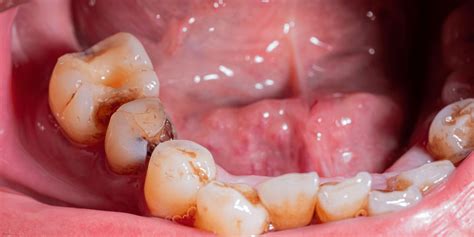

La caries entre los dientes se denomina «caries interproximal«. Un tipo de caries que suele afectar a muchos pacientes son las caries interdentales o interproximales. Las caries interproximales se forman en el espacio que hay entre las piezas dentales adyacentes. Por el lugar donde se originan, las caries interproximales pueden ser menos visibles y difíciles de detectar.

Este tipo de caries suele ser más peligroso que las que aparecen en los molares. Suelen ser más complicadas de detectar, puesto que en sus inicios no se pueden percibir a simple vista. La zona que está entre los dientes es más inaccesible y durante el cepillado dental será más difícil de limpiar. Por lo tanto es una zona propensa a la acumulación de placa bacteriana y sarro que provoca las caries.

En muchos casos si el paciente no suele acudir con frecuencia a su clínica odontológica y no se realizan ni revisiones ni limpiezas, las caries interproximales no serán detectadas a tiempo y se extenderán. Muchos pacientes se dan cuenta de que tienen una caries interproximal cuando ya sienten síntomas de dolor y sensibilidad dental, momento en que la caries ya ha erosionado parte de la estructura dental.

- Aparición de cavidad entre los dientes.